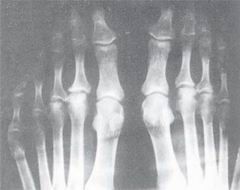

關節炎1、用於腎上腺功能不全所引起的疾病、類風濕性關節炎、風濕性發熱、痛風、支氣管哮喘等。用於過敏性皮炎、脂溢性皮炎、瘙癢症等。長期大量服用引起柯興氏征、水鈉瀦留、精神症狀、消化系統潰瘍、骨質疏鬆、生長發育受抑制。